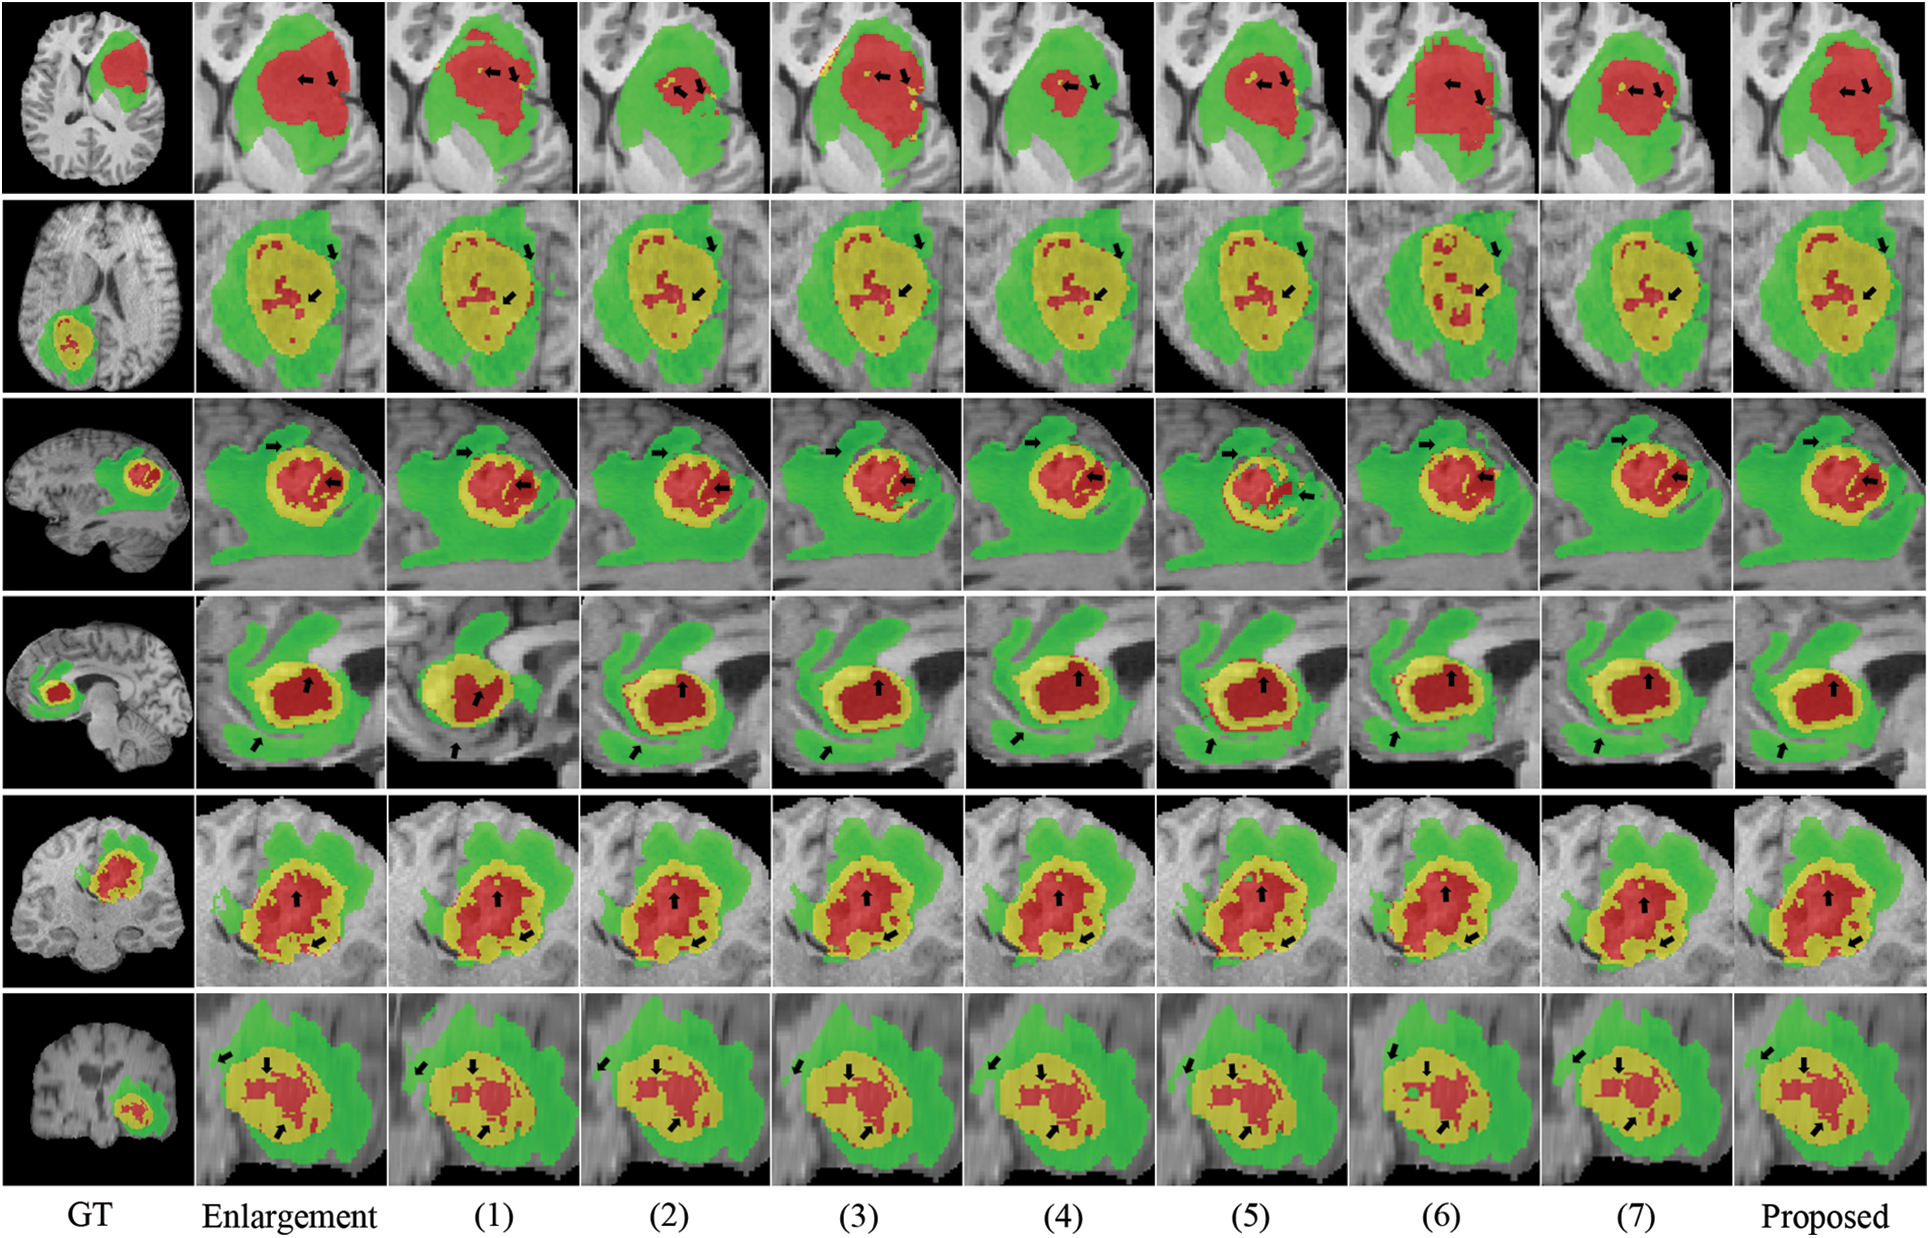

Fig. 4 depicts the box diagrams of the experiment’s DSC value results. A box plot visually represents the data’s dispersion, revealing its extent. The horizontal lines in the boxplot represent the maximum, upper quartile (Q3), median (Q2/median), lower quartile (Q1), and minimum, in descending order, from top to bottom. The proposed method generally achieves higher Q1, Q2, and Q3 values, indicating effectiveness. Observing all ET segmentation results, there is typically a large gap between the maximum and minimum, meaning difficulty segmenting the ET section and glaring differences between samples; however, the proposed method has higher DSC values. The concentration of the proposed method ranks third in TC segmentation, which may be due to the lack of preprocessing and postprocessing. However, it has a high value of Q1, Q2, and Q3 and validated its effectiveness. The proposed method manifests optimally in terms of WT segmentation. Fig. 5 shows the quantitative comparison of the experiments. The green regions represent peritumoral edema, the red regions represent gangrenous tissue, and the yellow regions represent tumor enhancement. According to the respective labels: WT is made up of green, red, and yellow regions; TC is made up of yellow and red regions; and ET is made up of yellow regions. Each row in the figure represents an MRI slice of a patient: the first and second rows correspond to the axial slices, the third and fourth rows correspond to the sagittal slices, and the fifth and sixth rows correspond to the coronal slices. The first and second columns of the figure are actual identifiers, with the second column containing a magnified portion of tumors. Small arrows are drawn on the diagram to denote the reference and comparison observation locations for the convenience of observation. It is shown in the figure that the proposed method improves the segmentation performance and performs better in terms of details. Specifically, the case in the first row does not contain enhancing tumors, but the proposed method still obtained excellent segmentation results.

Figure 5: Visualization of quantitative comparison of comparison experiments

We conducted several ablation experiments to evaluate the superiority of each proposed module. Table 2 shows the results of ablation studies. Method (1) utilizes the baseline model without the proposed MScAM. Method (2) uses a single Swin Transformer branch instant of dual-stem Swin Transformer branch and connects all the MRI modalities as one input, and the inputs of MScAM are replaced with the outputs of Swin Transformer layers. Method (3) shows the baseline model without CNNs branch in the encoder phase. Since TDsM is related to the CNNs encoder branch, method (3) does not contain TDsM. Method (4) replaces TDsM with max pooling, which is commonly used in deep learning. Method (5) utilizes the dual-stem Swin-Transformer branch without the CNN encoder branch and removes the skip connections. Method (6) only utilizes the CNNs encoder branch with TDsM for down-sampling. Method (7) utilizes a single CNNs encoder branch without TDsM. Method (8) excludes the Swin Transformer branch and TDsM. It expands the CNN encoder branch to dual stems and inputs grouped MRI images like the dual-stem Swin Transformer branch to verify the validity of MRI Pairing and MSCAM. Fig. 6 shows the visualization of the quantitative comparison of ablation experiments. Similar to Fig. 5, WT is made up of green, red, and yellow regions; TC is made up of yellow and red regions; and ET is made up of yellow regions. Each row in the figure represents an axial slice of an MRI image. The first and second columns of the figure are actual identifiers, with the second column containing a magnified portion of tumors. It is shown in the figure that the proposed method improves the segmentation performance and performs better in terms of details.